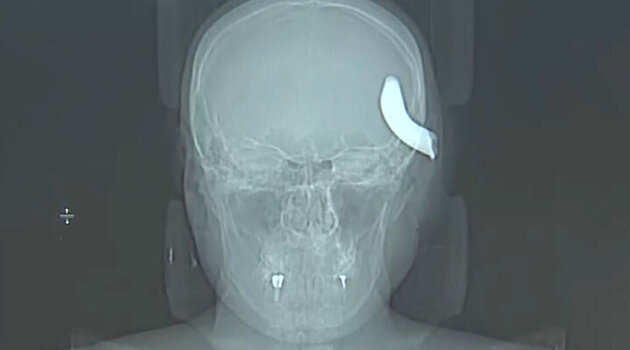

В Петербурге нейрохирурги извлекли из черепа молодого мужчины металлический крюк от буксировочного троса